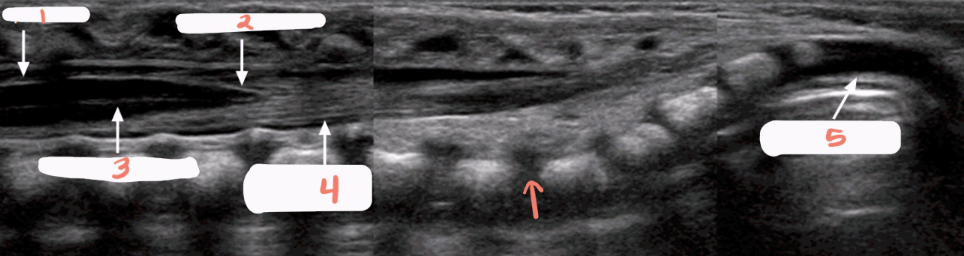

1

spinous processes

2

subarachnoid/dural layer

3

subarachnoid space filled with CSF

4

posterior margin of spinal cord

5

spinal cord with central echo complex

6

anterior margin of the spinal cord